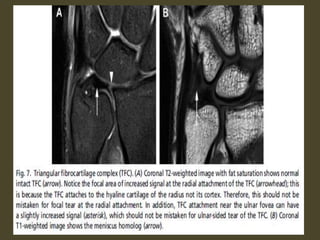

Triangular fibrocartilage complex tear.

Acute TFCC tear on FS T2-WI (A) and T1-WI (B).